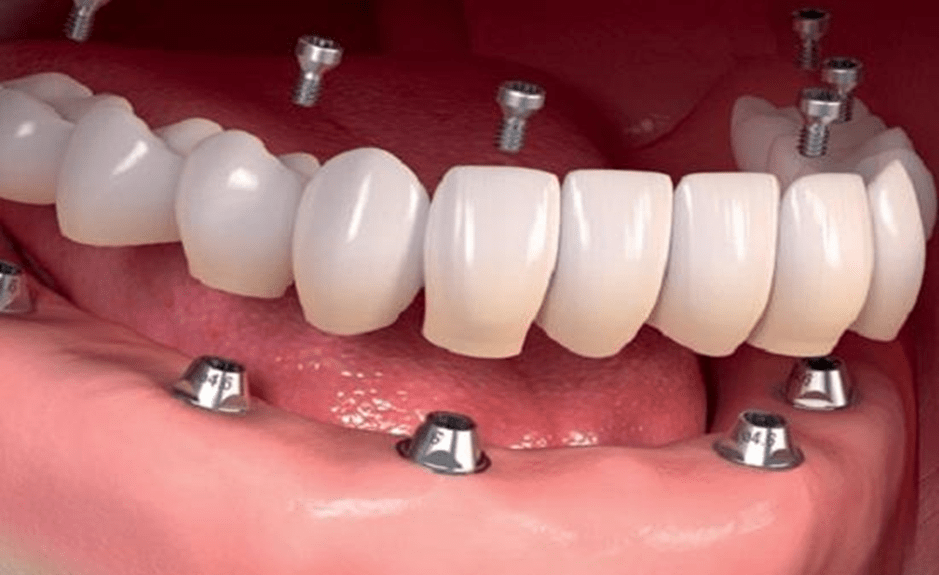

کاشت دندان یا ایمپلنت به این معنا است که فرد با انجام آن قصد دارد جای خالی یک یا چندین دندان را پر کند. ایمپلنت کامل دهان را میتوان شیوهای ساده برای جایگزین کردن دندانهای آسیب دیده یا از دست رفته دانست. آنها عملکردی شبیه به ریشه دندان خواهند داشت و از پایهای مستحکم جهت اتصال به فک برخوردار هستند. در شرایطی که عدم وجود دندانها در یک فک یا هر دو فک گسترش داشته باشد، فرد از شرایط استفاده از ایمپلنت کامل دندانی برخوردار خواهد بود. مزیتهای این روش در مقایسه با سایر درمانهای سنتی همچون دندان مصنوعی بسیار هستند. انواع مختلفی از ایمپلنت کامل دهانی نیز وجود دارند.

پیش از انجام ایمپلنت کامل دهان، شرایط و وضعیت دهان شما مورد بررسی قرار میگیرد. در روش فول موس بسته به شرایط خاص دهانی شما، امکان دارد که به چهار تا هشت ایمپلنت در فک بالا و چهار تا هشت ایمپلنت در فک پایین نیاز داشته باشید. این روش درمانی برای افرادی به کار گرفته میشود که جای خالی بسیاری از دندانها را در دهان خود حس میکنند. در این شیوه از درمان، ایمپلنت دندانی در استخوان فک قرار داده میشود و دیگر پروتزهای دندان تحت حمایت این ایمپلنتها قرار میگیرند.